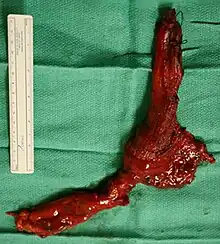

End-stage achalasia, typified by a massively dilated and tortuous esophagus, may occur in people previously treated but where further dilatation or myotomy fails to relieve dysphagia or prevent nutritional deterioration, and oesophagectomy may be the only option. We describe two patients with end-stage achalasia and nutritional failure despite exhaustive conventional therapy including pneumatic dilatation and surgical myotomy. Both patients were successfully managed with transhiatal oesophagectomy and cervical gastro-esophageal anastomosis, with excellent symptomatic control and improved quality of life. These cases are discussed and the literature reviewed.[10]

End stage disease, characterised by a markedly dilated and tortuous "burned- out" oesophagus and recurrent obstructive symptoms, may require oesophageal resection in order to restore gastro-intestinal function, reverse nutritional deficits and reduce the risk of aspiration pneumonia.[11][12][13]